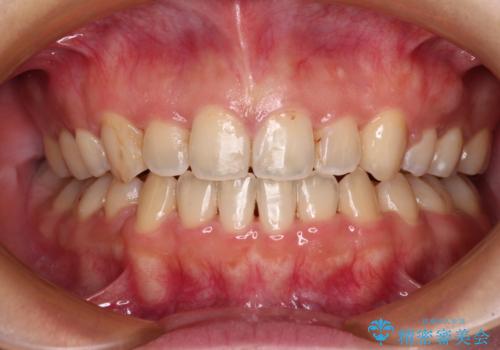

八重歯を抜歯矯正でスッキリと メタルブラケットでの矯正治療

八重歯で口元が膨れている ワイヤー装置での抜歯矯正

重度のガタガタと出っ歯をワイヤーによる抜歯矯正で整った歯並びへ

八重歯をインビザラインで非抜歯矯正